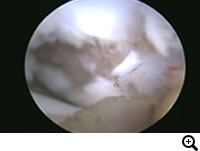

前十字靭帯断裂とは

膝関節の安定化を担っている前十字靱帯が断裂することにより、膝関節の不安定性が発現します。断裂した前十字靱帯の断端から炎症性のメディエーターが放出されるため、関節炎が起こります。

診断

触診、レントゲン検査、関節鏡検査

関節外制動法(Lateral Suture Stabilization)など。前十字靭帯と同様の働きをする位置に合成靭帯を設置し、膝関節を安定化させる手術法。

OCD(離断性骨軟骨症)とは

大腿骨骨頭の関節軟骨が成長障害により厚みを増し、損傷を受けやすくなり、軟骨が浮きあがりはがれることで痛みを生じます。

レントゲン検査、関節鏡検査

治療

OATS(自家骨軟骨移植)など。軟骨の欠損部に別の部位から採取した本人の正常な軟骨を移植し、関節面での接触を良くし、痛みを取り除きます。大型犬の成長期の跛行は消炎鎮痛剤等による対症療法ですませず、跛行原因の早期診断、早期治療が重要です。